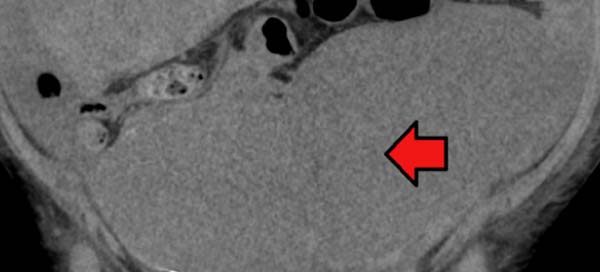

Los síntomas “sutiles” de cáncer de colon que podrían salvar vidas por el diagnóstico temprano

Según el informe Las cifras del cáncer en España 2019 realizado [...]